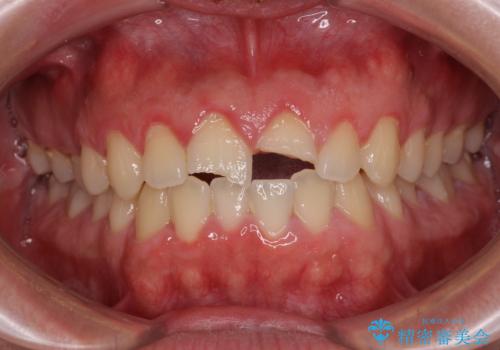

- 酔っ払って転んだらしく、目が覚めたら病室で歯が欠けていたとのことで来院された患者様です。

痛みを感じており、歯の欠けている状況から、神経組織のダメージも想定されました。

無菌的環境下にて歯の状態を調べ、最終的にオールセラミッククラウンにて補綴治療を行うこととしました。

幸いにも神経組織に影響はなく、健全な状態で治療を終えることができました。

歯肉の腫脹が目立っていたため、衛生指導も並行して行い、引き締まった歯肉になりました。